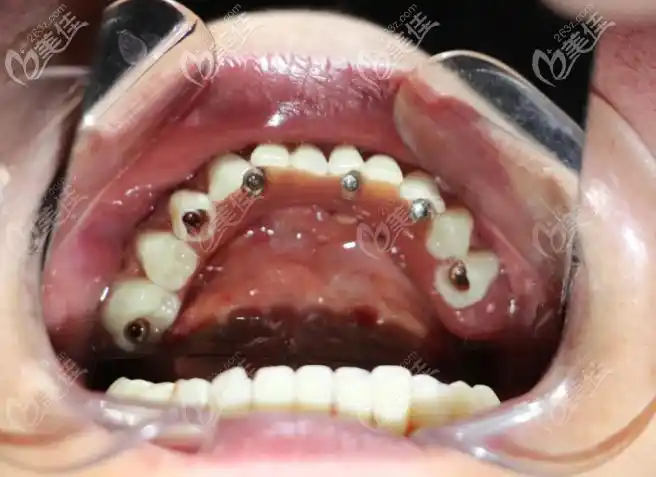

即刻拔牙后做半口瑞士士卓曼钛锆亲水种植牙,花了8.8万

种植牙修复过程中常出现的并发症及其处理_医学界-助力医生临床决策和